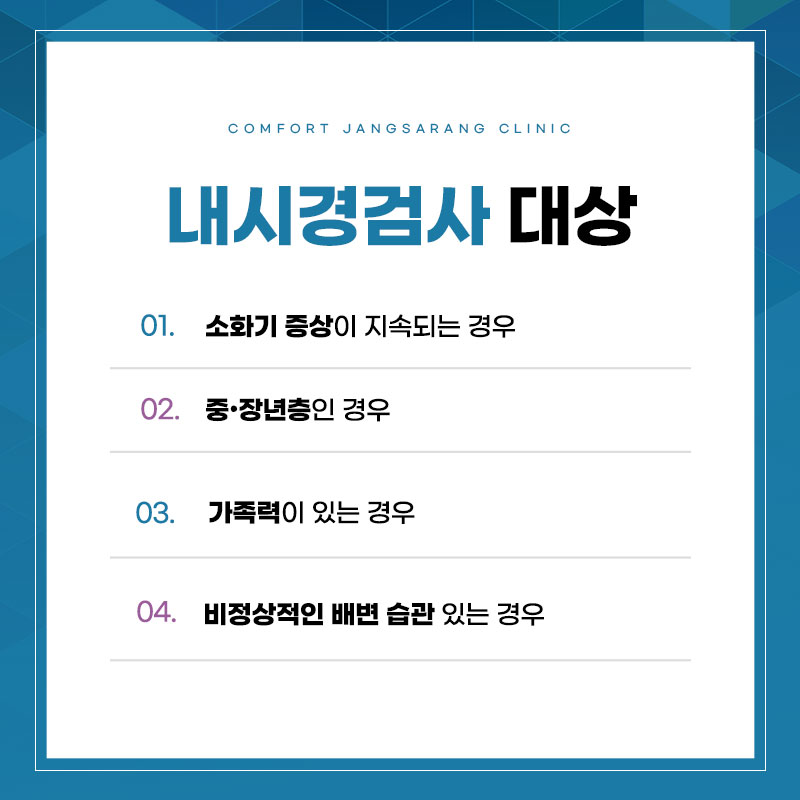

복통이나 설사, 변비 같은 증상이 반복되면

장에 문제가 있는 건 아닌지 고민하게 됩니다.

그럼에도 불구하고 증상이 잠시 나아졌다는 이유로

대장 검사를 미루는 경우가 많습니다.

하지만 대장은 이상이 생겨도 초기에는

뚜렷한 신호 없이 지나가는 경우가 많습니다.

복통, 설사, 변비, 혈변과 같은 증상이 반복된다면

증상을 가볍게 넘기기보다는

청주대장내시경 검사를 통해

장 상태를 점검해보는 것이 도움이 될 수 있습니다.